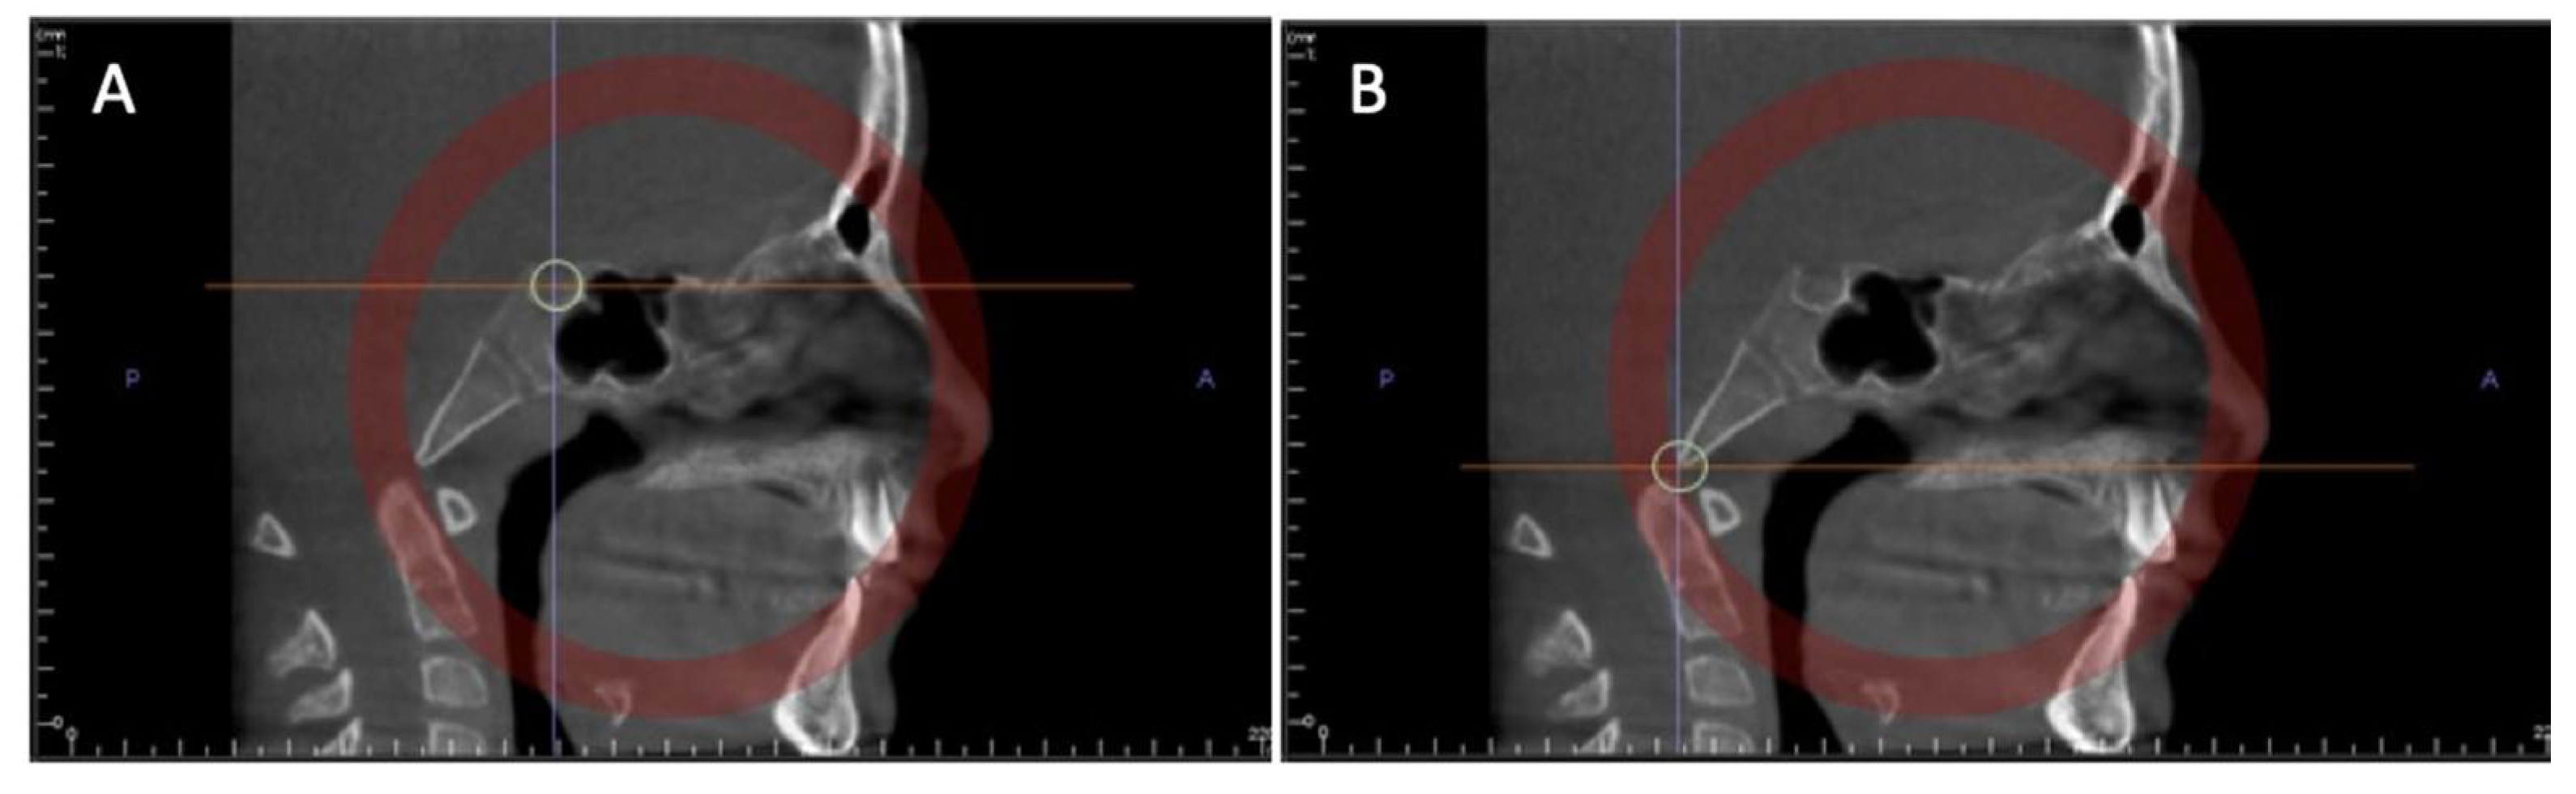

2.1.3. 3D Imaging and Spheno-Occipital Synchondrosis Ossification